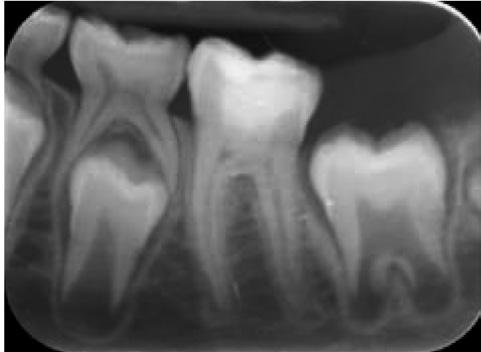

106 Tooth surface protectionfrom concept to clinic

112 The 3D printed permanent crown - Are we there yet?

|

Online Resources for the Dental Profession...

More than 50 years ago during a course in restorative dentistry at the Eastman Institute in London, one of the instructors said something that had a profound impact on my dental career. He said that the primary aim of dental treatment should be to ensure that the patient retains a functioning dentition for life - it is not to enrich the dentist! Recently, there has been a lot of commotion in the profession regarding a push to allow pharmacists in Queensland to examine young patients and apply fluoride varnish. Clearly this is not an ideal situation, but it is one that has a lower potential for harm than the mail order orthodontics that are promoted through some of the pharmacy chains, or for that matter, the “Bleaching Boutiques” that are springing up in various shopping centres.